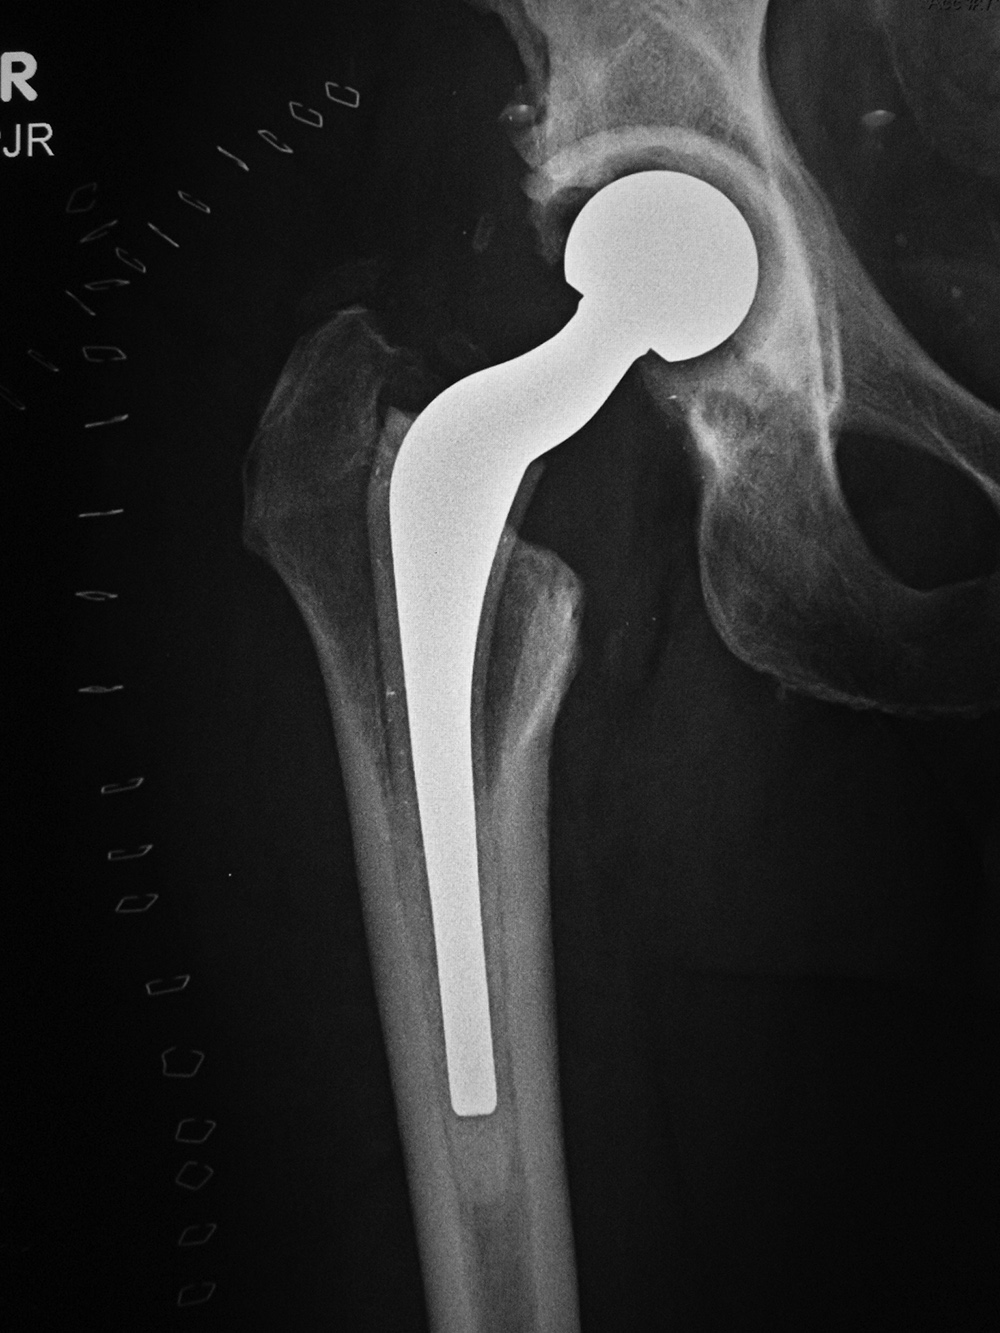

Non-infectious (aseptic) loosening of prosthetic components is

still the most common cause for hip implant failure and subsequent revision surgery. Loosening may be from mechanical stress with failure of the implant binding to the surrounding bone. There may be degradation of the cement-bone interface. Wear on the articular surfaces can produce tiny polyethylene particles or metallic particles which migrate from the joint and lessen bony healing giving subsequent osteolysis and eventual implant loosening (figure: focal osteolysis). The failure can occur at the prosthesis-bone interface, prosthesis-cement interface,

or cement-bone interface. Progressive development of radiolucent areas greater than 1 mm at these interfaces is worrisome for prosthesis loosening (figure: osteolysis at tip of femoral stem).

The femur has traditionally been divided into seven zones (1-7) on the anteroposterior (AP) view: zones 1-3 at the lateral side proximal to distal; zone 4 at the tip of the femoral stem; zones 5-7 at the medial side going distal to proximal. On the lateral view the femur is divided into zones 8-10 at the anterior side proximal to distal; zone 11 at the tip of the femoral stem; and zones12-14 on the posterior side going distal to proximal (figure: AP acetabular and femoral zones; figure: Lateral femoral zones). In any of these zones on any view, a radiolucent area greater than 2 mm is indicative of loosening (Berquist, 1995; Freiberg, 2001; Benjamin, 1994; Galante, 1998; Manaster, 1996; Deshmukh, 2019) (figure: femoral osteolysis).

| Focal osteolysis about femoral stem of total hip arthroplasty |

| Cemented total hip arthroplasty with focal osteolysis about the stem in zones, 2, 5, and 7. From Benjamin, 1994 |